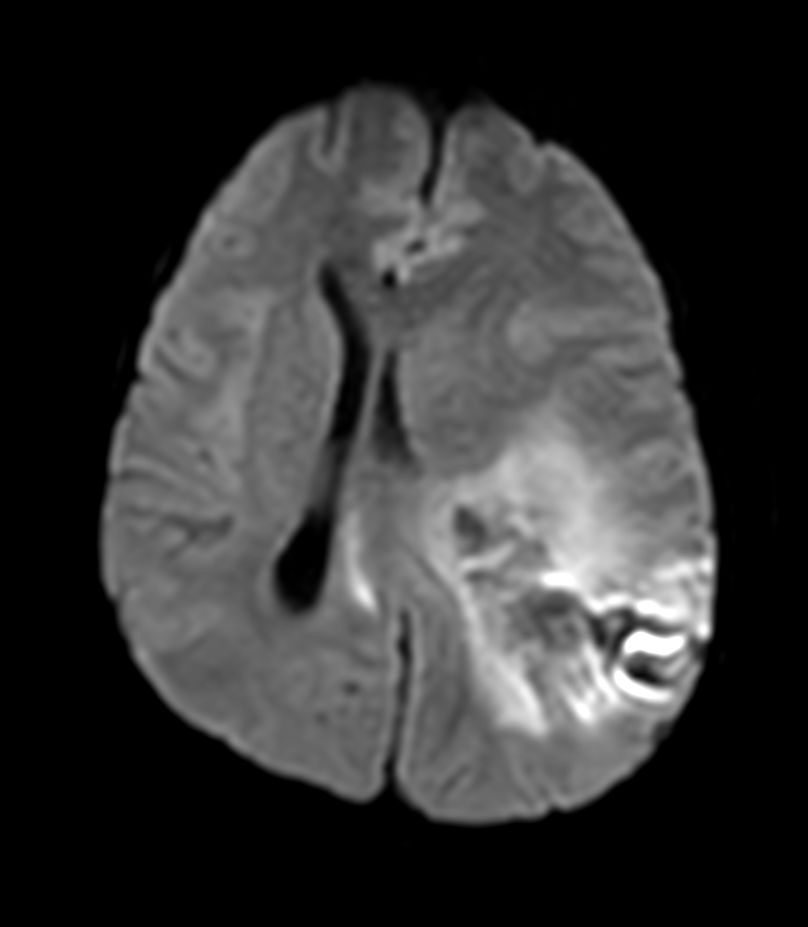

Pediatric Brain with hemorrhagic mass

Pediatric patient with a hemorrhagic mass in the brain